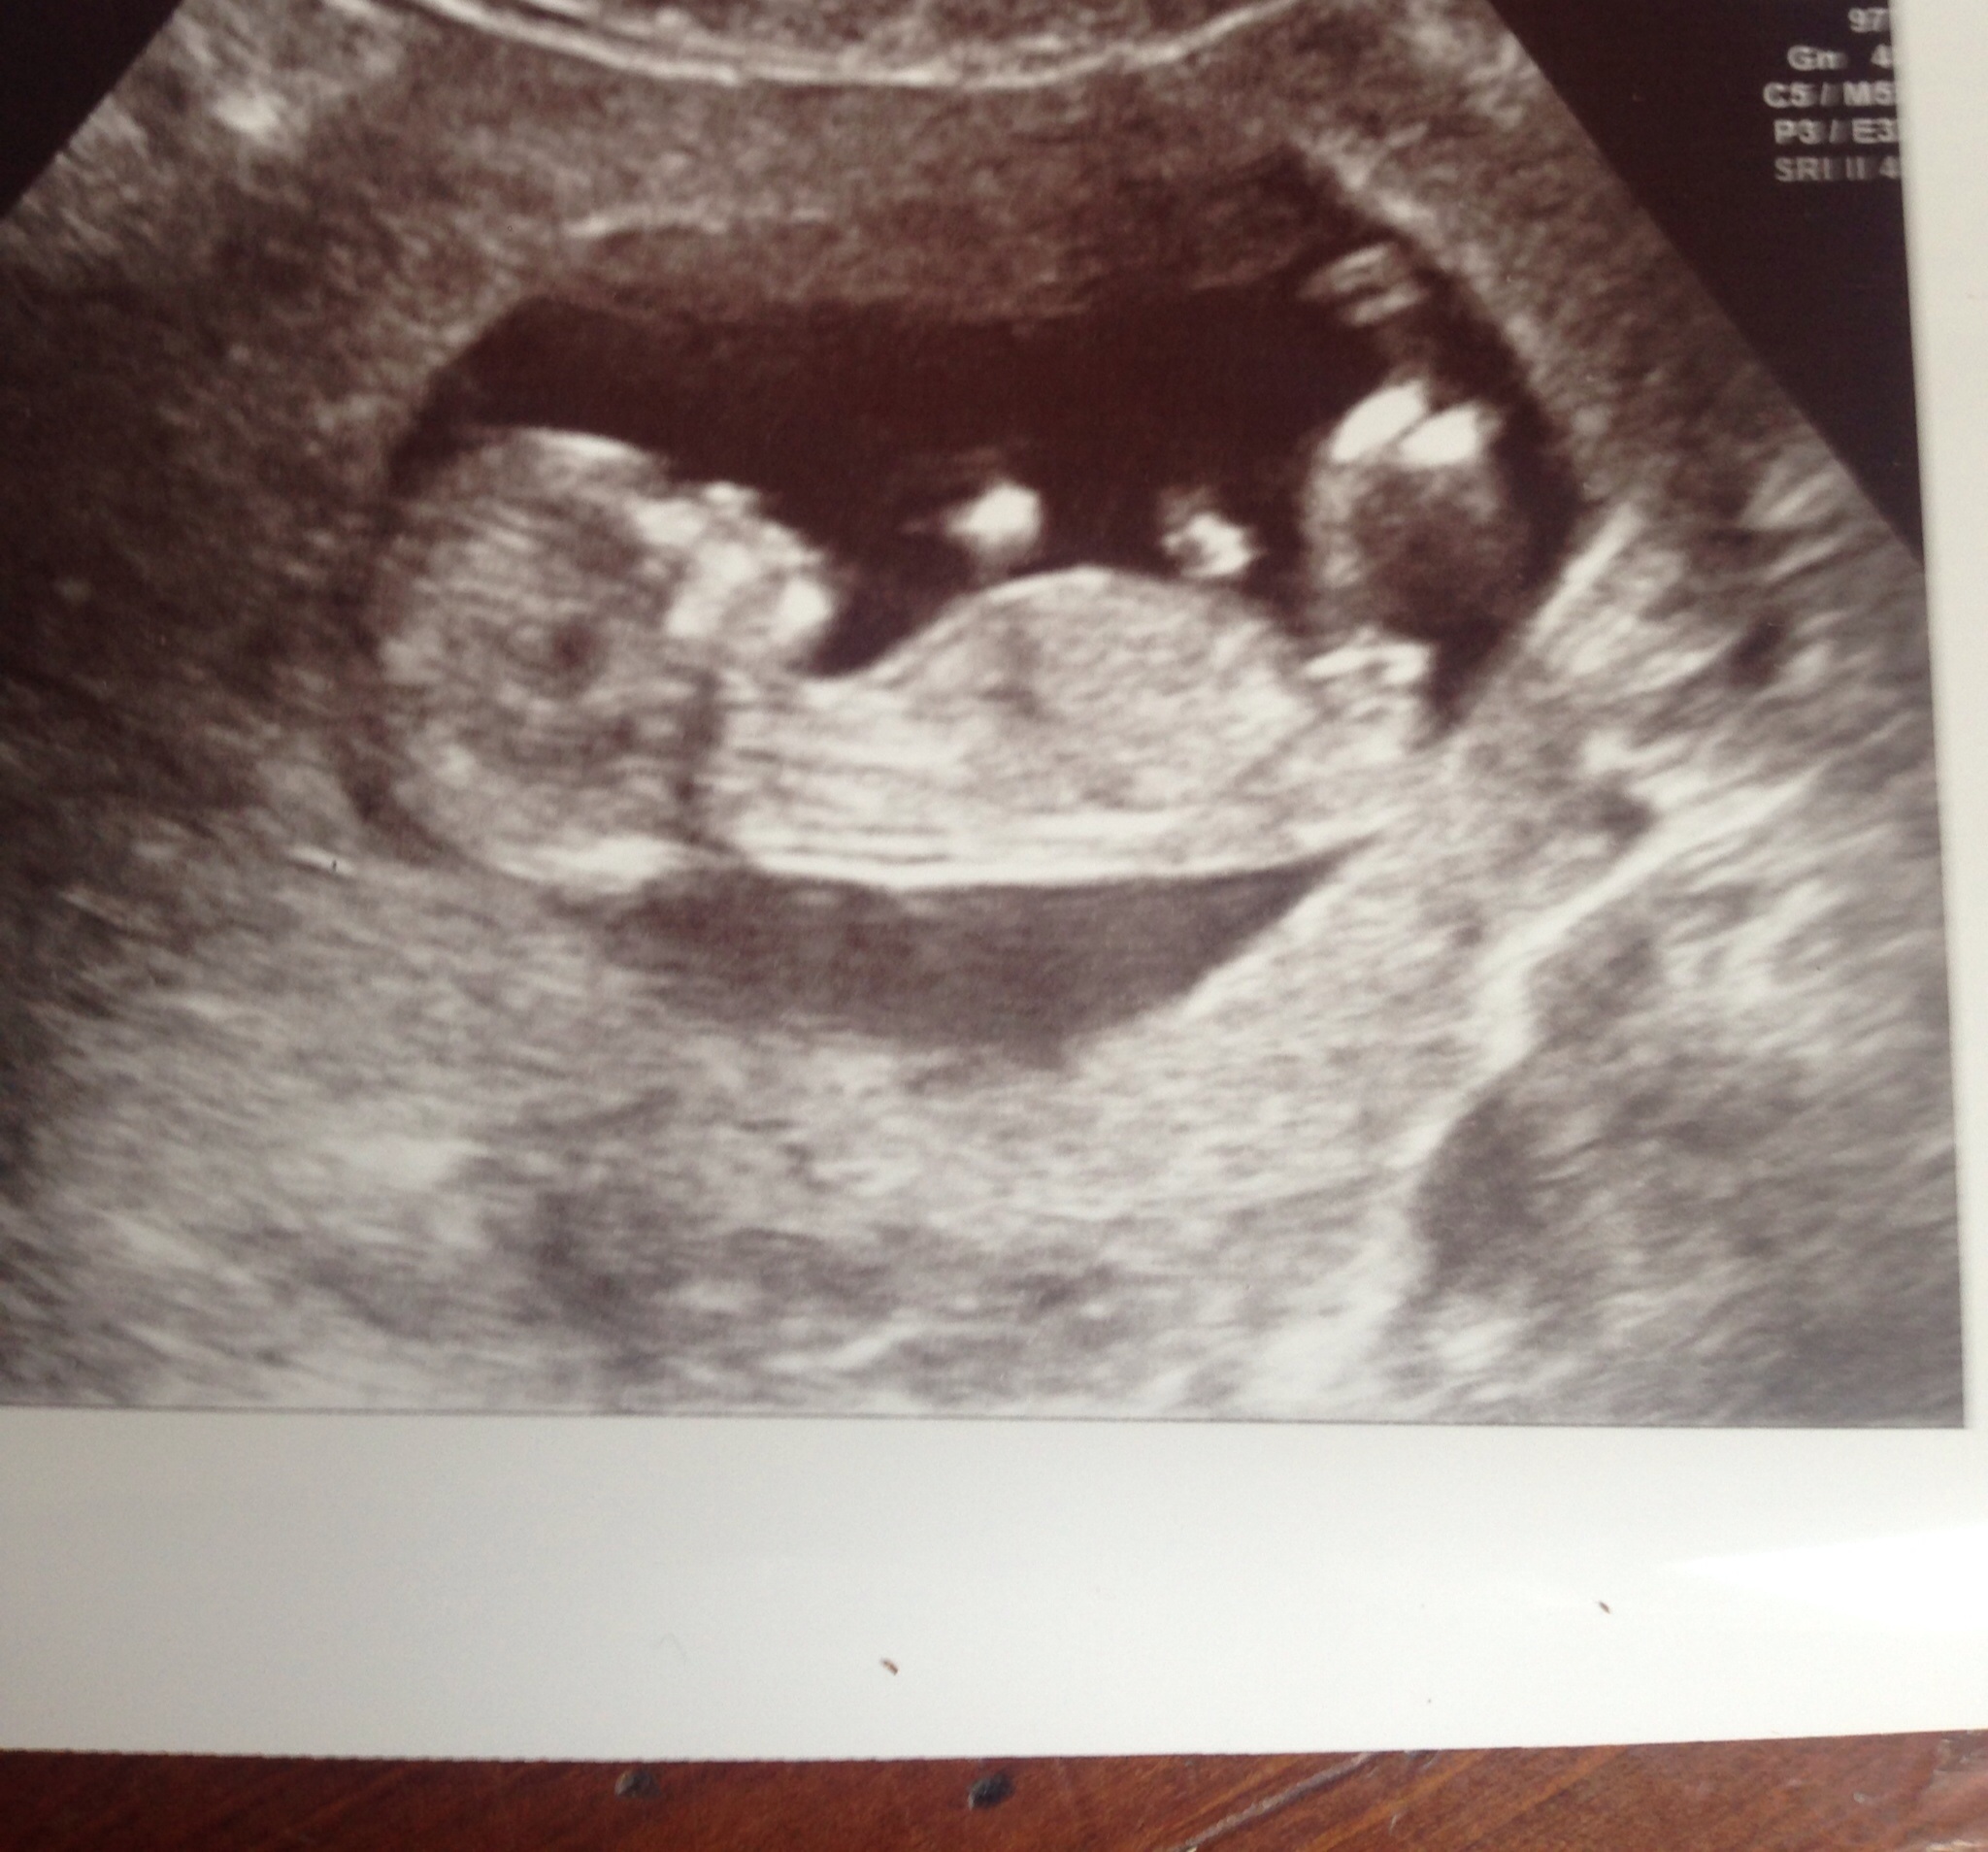

Last pic shows the most visible nub. I'd say def a girl, considering you're beyond 13 weeks.

If you were earlier, I'd have said boy. But given you are beyond 13 weeks, I think we would see more rise if it were a boy. So I tentatively lean girl.

Pink but I agree with above. If you weren't at 13 weeks I would have thought the nub was on the rise.